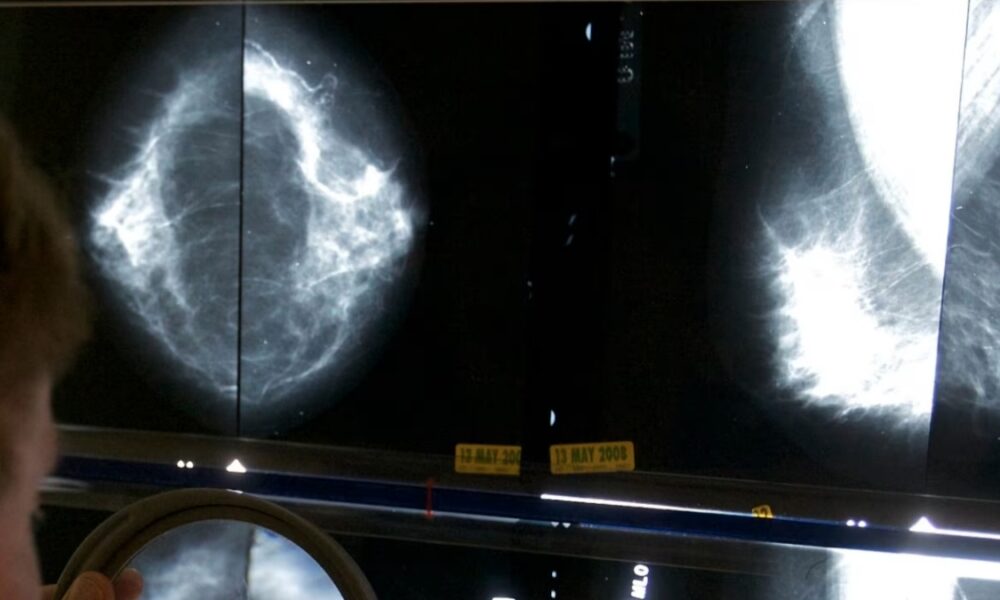

Este 19 de octubre se celebra el Día Mundial de la Lucha Contra el Cáncer de Mama y según datos de la Organización Mundial de la Salud (OMS), el esta...

La Organización Panamericana de la Salud (OPS) catalogó al cáncer de mama como el más diagnosticado entre las mujeres y a su vez representa la segunda...